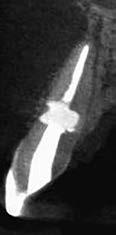

This element was not stimulated with the cold test and the radiographic image revealed an incomplete endodontic treatment (Figs. 1-2). The element seemed to present a suitable root length for a conservative restoration, but the apical position of the carious lesion and the proximity of the interdental bone ridge didn’t allow a correct rehabilitation with prosthetic crown, respecting the biological width.2

Figure 2: Initial radiograph showing endodontic dressing that had been present for some months, but the treatment was never completed. Note the depth of the caries lesion and the proximity of the interdental bone ridge, which may represent an obstacle for prosthetic rehabilitation.

The canal was sealed with a Thermafil™ cone (Dentsply Sirona) with an apical diameter of 0.30 mm (Figs. 3-4).